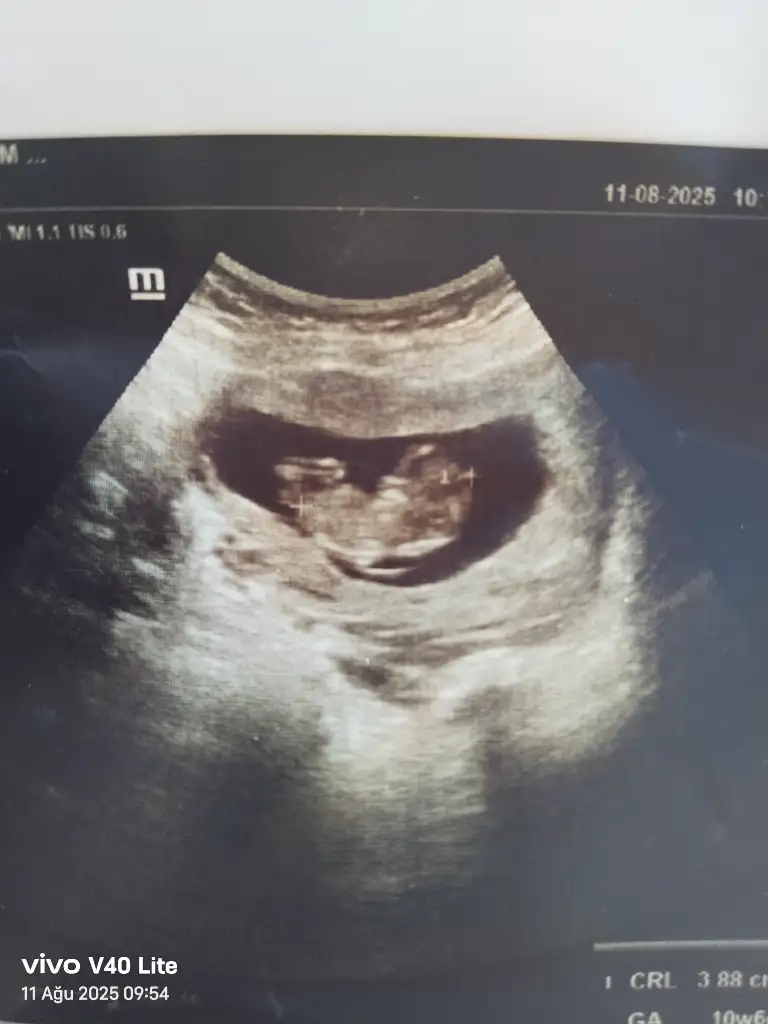

Merhaba benimde yorumlarmisiniz rica etsem 11+1Bariz erkek görüyorum, sağlıcakla gelsin inşallah![]()

Bir çoğunda ölçüm çizgisi o kısıma denk gelmiş ama, bir tanesinde kız gördüm sanırım, sağlıcakla gelsinMerhaba benimde yorumlarmisiniz rica etsem 11+1

Sizce benim nedir 11+1Erkek bence